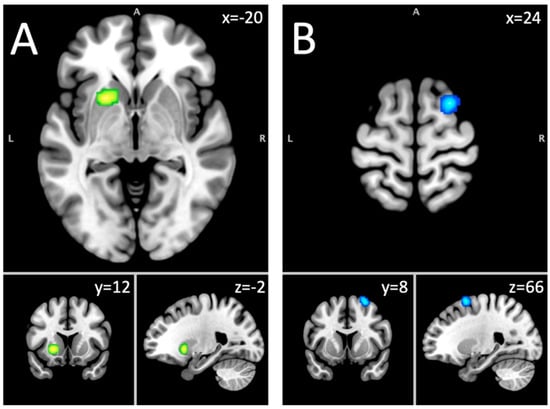

| Hyper–hypoactivation combined: whole sample | |||||

| Putamen, caudate body, caudate head | L | 1840 | 0.0367 | 5.66 | −20, 12, −2 |

| Hypoactivation: long-term abstinent sample | |||||

| Superior frontal gyrus, middle frontal gyrus | R | 856 | 0.0147 | 3.85 | 34, 56, 18 |

| Cingulate gyrus, medial frontal gyrus | R & L | 800 | 0.017 | 4.26 | 2, 26, 38 |